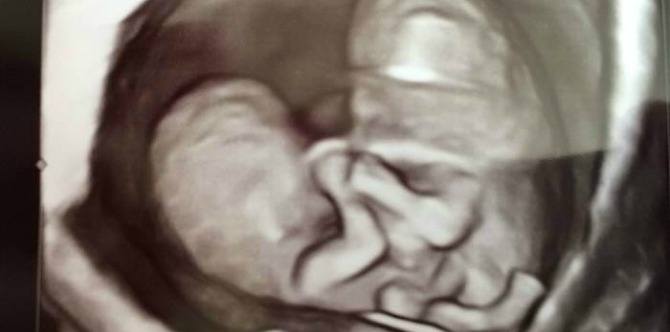

The odds are not in Chelsea and her husband Nick’s favor: months into their pregnancy, they found out that they were carrying conjoined twins, fused together at the chest and stomach, and they also likely share one pelvis.

At this stage of her pregnancy, the doctors believe that the twins have two hearts, two stomachs, and two spines, but their backs come together to share one pelvis.

Doctors also suspect that they share one bladder.